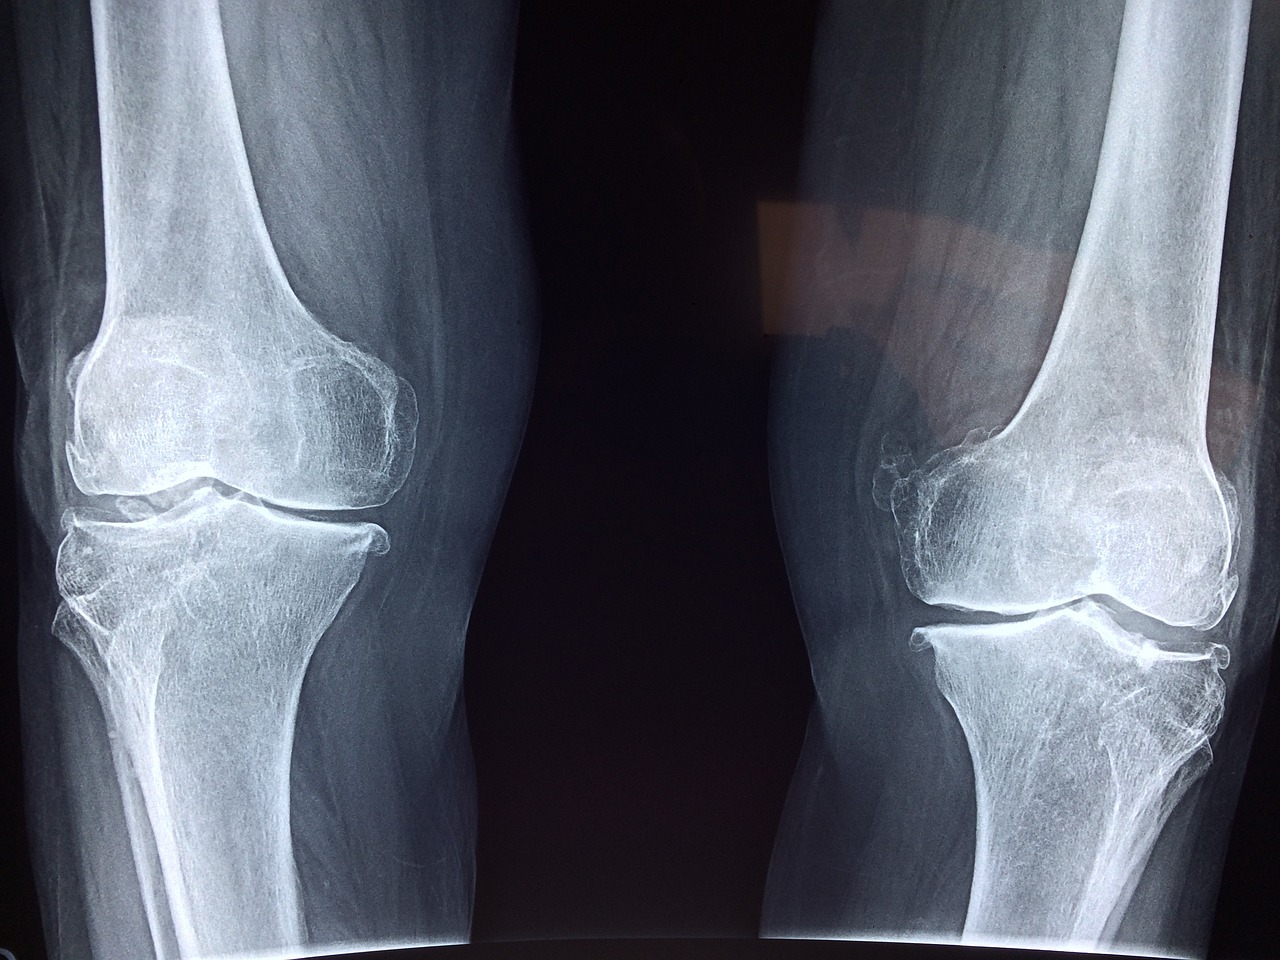

People may not notice osteoporosis until a bone is broken, so it receives the nickname “silent disease.” Among the signs are back pain, shrinking height, becoming hunched and having fragile bones mostly in the spine, hip or wrist. Most often, doctors use dual-energy X-ray absorptiometry (DEXA or DXA) to check for bone density impact. A scan is actually safe and simple and it's compares your bone mineral to set guidelines. Different blood and urine tests may be needed to find out if other things are causing the symptoms. Preventive screening is more important for high-risk women and older people, who should arrange it early if they can.